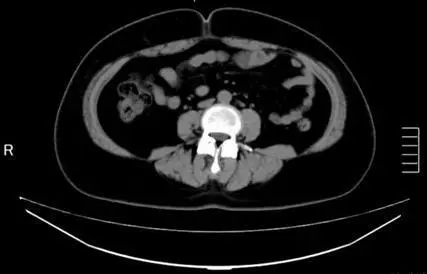

BEFORE

OurAge×Webエクラ BEFORE

体重 77.0kg

腹囲 103.0cm

体脂肪の量

全体 475.37㎠

内臓脂肪 192.25㎠

皮下脂肪 283.12㎠

AFTER

OurAge×Webエクラ AFTER-2

体重 75.0kg   −2.0kg

腹囲 101.0cm   −2.0cm

全体 457.23㎠    −18.14㎠

内臓脂肪 177.80㎠ −14.45㎠

皮下脂肪 279.43㎠ −3.69㎠

「Cさんは、3週間〈齋藤式満腹やせメソッド〉を実践する前に、すでに1カ月間、食事にMCTオイルを取り入れていたそうで、その時点で体重が1.5kg落ちたようです。ですからもともとの体重は78.5kgで、その後〈齋藤式満腹やせメソッド〉を実践して75kgまで落ちているので、体重は3.5kg落ちたということ。

しかも、〈齋藤式満腹やせメソッド〉をそこまで厳密に行ったわけでなく、とにかく、MCTオイルを食事に足すようにしたそう。それだけでも、3週間で内臓脂肪は14.45㎠、皮下脂肪は3.69㎠も減少したので、MCTオイルの効果の高さがわかりますね。CT検査の画像でも内臓脂肪が落ちていることがよくわかります。また、〈齋藤式満腹やせメソッド〉実践前は中性脂肪値が214mg/dlと基準値以上だったのですが、実践後は126mg/dlと正常値になったのもすばらしい変化。続けることで、さらに効果が表れると思います」